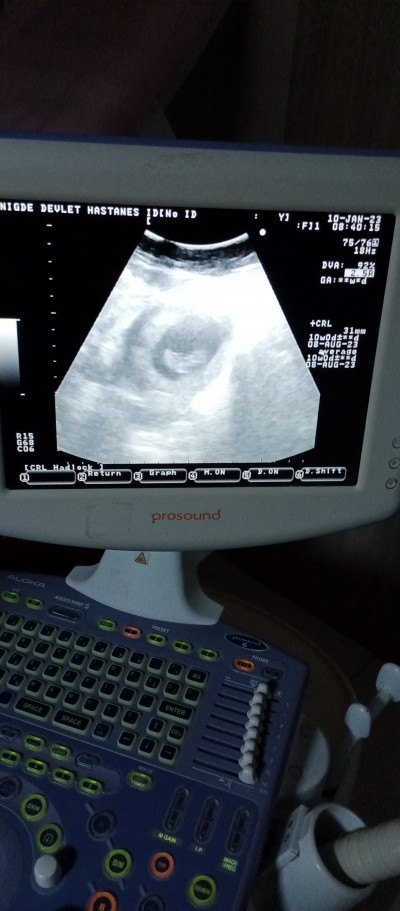

Kızlar 10haftalik hamileyim ama bebek bu şekilde bunun kolu bacağı yok niye ben bişey anlamadım ama bu uygulamanın 10 haftalık ultrason görüntüsünde kol bacak var bunda yok doktor gayet iyi dedi 2 hafta sonra ikili test için çağırdı

Gebelik haftası 10